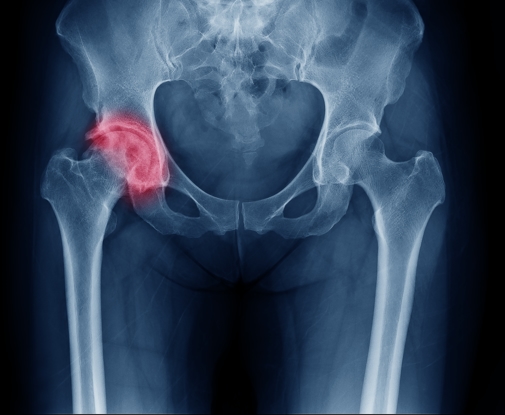

Injury, arthritis, illness or normal wear and tear can cause joint pain. Screenings are designed to help pinpoint the cause of your pain and provide ...

As we age, so do our bones. Fragile and weakness of bones can lead to osteoporosis in women after menopause and in older men. This bone-thinning ...